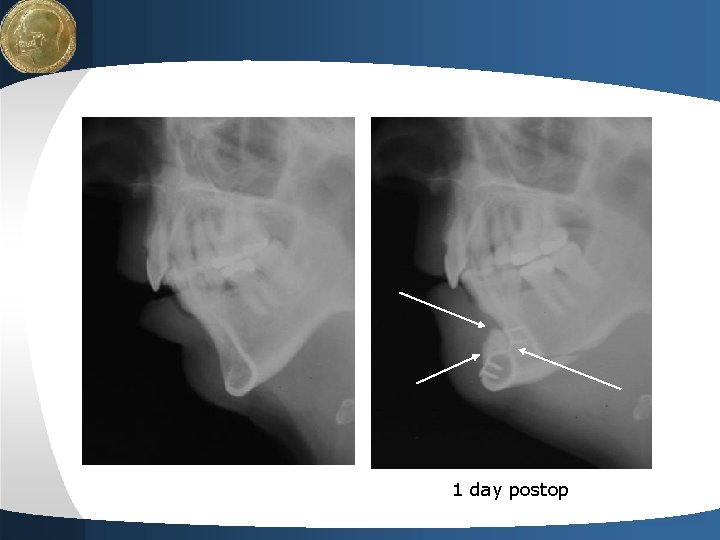

LOGO Chin osteotomy - anterior step text 2 Your site here

LOGO 1 day postop Your site here